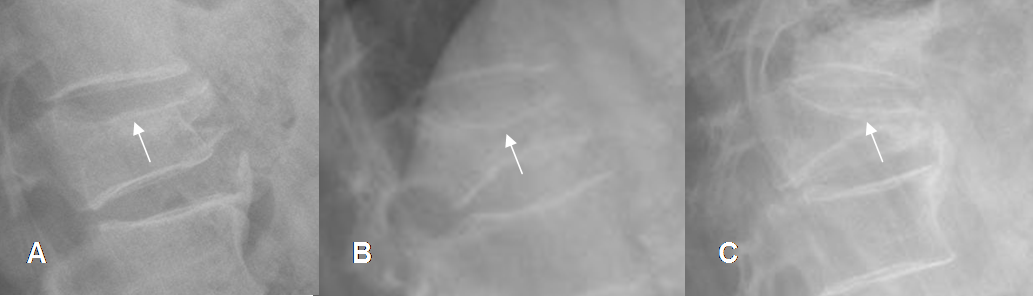

Fig 216. Fracturas.

Rx lateral. Gran osteopenia generalizada, con pérdida de altura en varios cuerpos vertebrales.

En D12 se ha perdido la placa terminal superior (Flecha delgada) y la placa superior de L2 es densa (Punta de flecha), lo que hace sospechar evolución aguda. Cortical normal en el borde superior de L1, por probable evolución crónica. (Flecha gruesa).